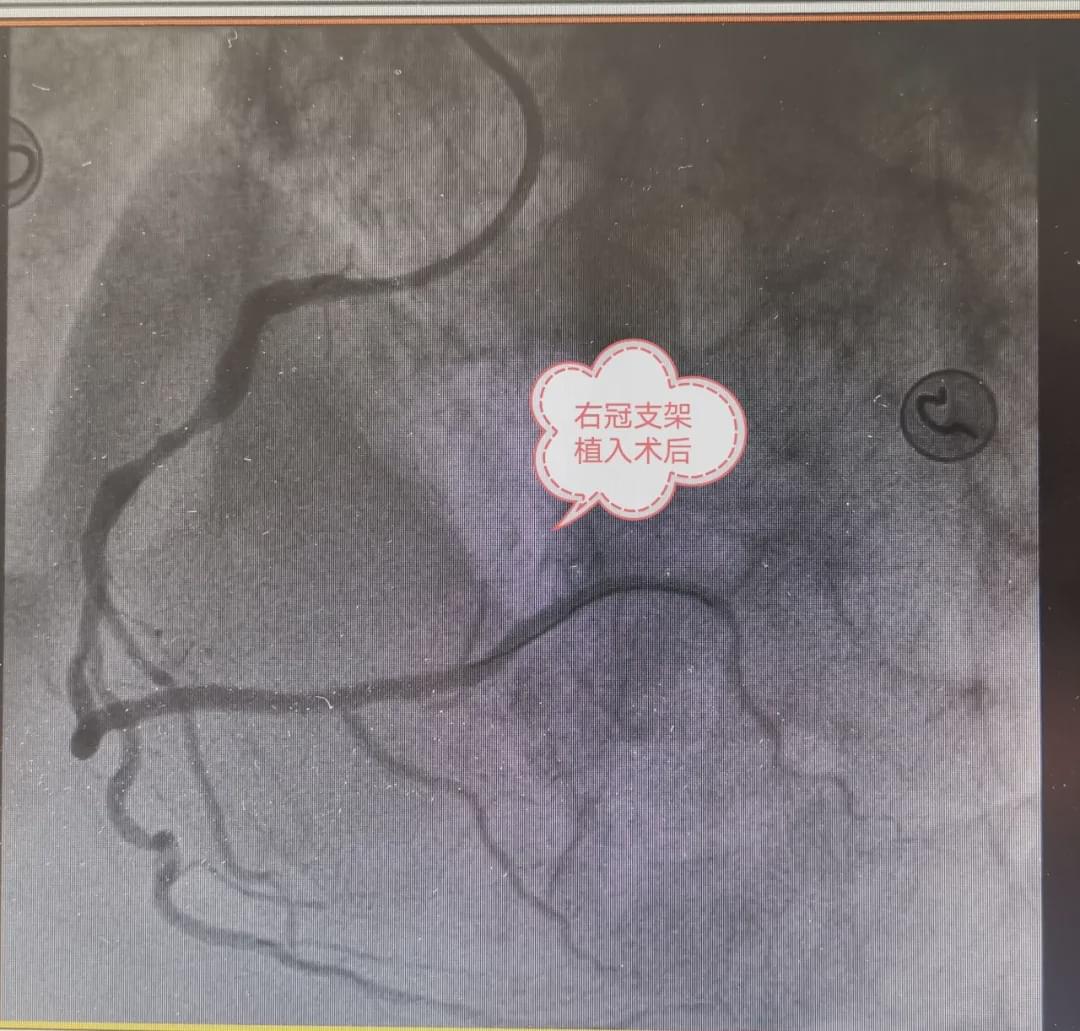

患者进入手术室后,立即给予消毒、心电监护、吸氧,手术医生开始穿刺、顺利造影完毕,造影显示患者严重三支病变,根据心电图结果考虑此次疾病为右冠状动脉中段完全闭塞所致,立即为患者开通血管,在导丝通过时才发现闭塞部位血管严重迂曲、260°成角畸形,应用球囊支撑,导丝勉强到达远端,造影显示不清楚,无法判断导丝在真假腔内,如果进入假腔,行支架术,将导致冠脉夹层,手术失败,患者发生猝死风险极高,丁水印主任立即下指令,应用血管内超声明确远端导丝的具体位置,介入手术室护士周程昊立即启动仪器,超声显示远端导丝穿入假腔后又进入真腔,在血管内超声的引导下,及时调整了导丝的位置,很快进行球囊扩张及支架植入术,患者右冠状动脉血流通畅,远端血管粗大,患者症状很快改善,生命体征稳定,此时患者从进入医院大门到血管开通,仅用时38分钟!